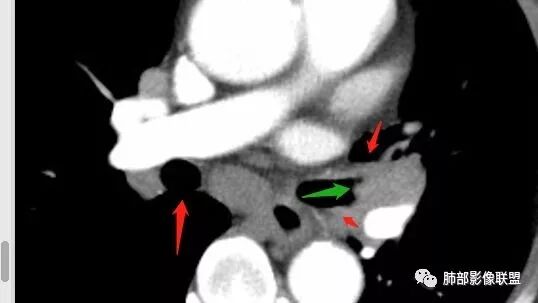

南边:但是我们看纵隔就多发的肿大淋巴结,部分融合成团。

南边:而且这些淋巴结,有些直接主要是压迫支气管壁,但是有些是突入到支气管腔内的。可惜我截的图发不上来。就左上舌段,支气管壁明显的增厚。有些明显腔内突的一个结节的,但是远的没有阻塞的特点。南边:增强以后呢,这个病灶明显强化,部分的似乎有环形强化的迹象,但不是很典型。

我们看这个主支气管的层面,主支气管明显受压,有变形的,但是软骨是没有突破的。

南边:那也就是说,这个纵隔淋巴结,它是没有影响到我们主支气管内部去的,周围有,可惜的膜部的增厚,我总心里不踏实,后面因为食道贴在一起啦。 因此这些淋巴结在主支气管层面是没有影响的。

但是有一个地方有问题的,左侧的上叶的下舌段这个区域:

左上叶舌段这个气管腔内是有东西凸进去。